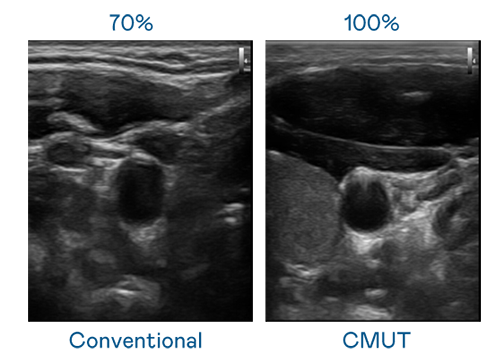

CMUT 技術是一種用電容式微機電元件來產生超音波訊號的技術。與傳統 PZT 壓電式技術相比,CMUT 頻寬增加 30%,更寬頻的超音波訊號讓影像解析度大幅提升,是實現高影像品質醫療超音波掃描、促進精準醫療發展的關鍵技術。

超音波影像的解析度高低,首先取決於探頭能發出的訊號頻寬。AG亚游 CMUT 可提供高清晰的超音波訊號,提供高頻寬、高靈敏度、影像紋理細節更高的超音波影像,協助醫護人員縮短影像判讀時間及利用精準的醫療影像進行診斷。